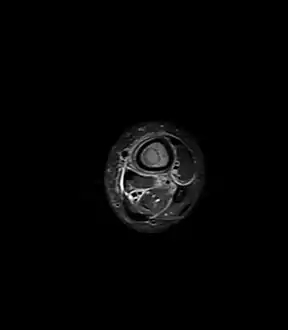

Fat saturated STIR (short tau inversion recovery) image showing hyperintense edema in the calf musculature, marrow edema, and subperiosteal pus. The intramedullary abscess cavity is hyperintense as well. Fat saturated STIR (short tau inversion recovery) image showing hyperintense edema in the calf musculature, marrow edema, and subperiosteal pus. The intramedullary abscess cavity is hyperintense as well.